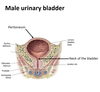

Where are the 3 potential sites of obstruction of the ureters in case of kidney stones?

- at the junction of the ureters and the renal pelvis

- where the ureters cross the brim of the pelvic inlet

- during their passage through the wall of the bladder

4? 5? 6?

4? 5?

3? 4?

1? 2?

25? 26?

5? 6?

9? 10? 11? 12?